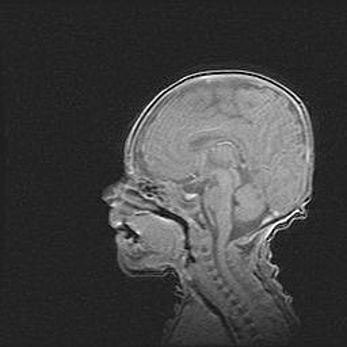

Аномалия Денди-Уокера. Признаки гипоплазии мозолистого тела.

Возраст: 5 месяцев 3 дня

Вес: 5550 г

Пол: мужской

Окружность головы: 39 см

Срок гестации: 40 недель

Аномалия Денди-Уокера – это порок развития головного мозга, для которого характерна триада симптомов: гипотрофия или аплазия червя мозжечка и/или полушарий мозжечка, расширение четвёртого желудочка с формированием ликворной кисты задней черепной ямки, гипертензионная гидроцефалия различной степени.

Гипоплазия мозолистого тела относится к дефектам внутриутробного этапа развития мозговой ткани, возникающим в процессе закладки структур головного мозга, что происходит на начальных этапах развития эмбриона.